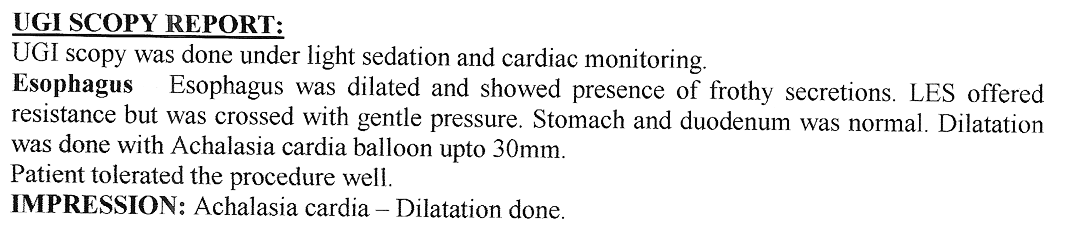

Strong contractions of the food pipe is known as dysmotility of esophagus and an unusual condition known

as Achalasia Cardia due to powerful contraction of the valve of the esophagus at its lower end which

can cause difficulty in swallowing.

Achalasia Cardia - Balloon Dilatation

Achalasia Cardia - Balloon Dilatation

Achalasia Cardia - Balloon Dilatation

Achalasia Cardia - Balloon Dilatation